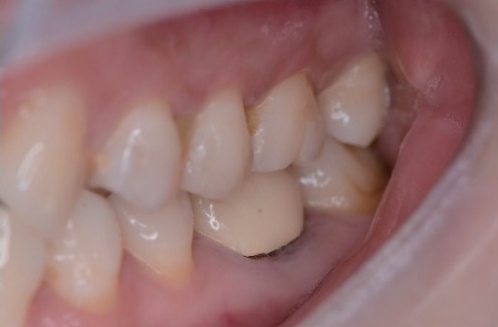

显微根尖手术联合引导组织再生术治疗左上前牙根尖囊肿1例及3年回访

病史摘要:43岁女性,因“左上前牙牙松动”就诊,左上前牙曾在外院行根管治疗,时间不详。否认心血管疾病、糖尿病等系统性疾病史,否认肝炎等传染性疾病、药物过敏及精神和心理病史。口腔卫生差。诊疗过程:口腔检查发现多颗牙齿存在不同程度的问题。根尖片和CBCT显示21、22根尖周有大面积阴影等情况。诊断为12继发龋、21和22慢性根尖周炎。治疗方案包括12充填治疗,21显微根管治疗,22显微